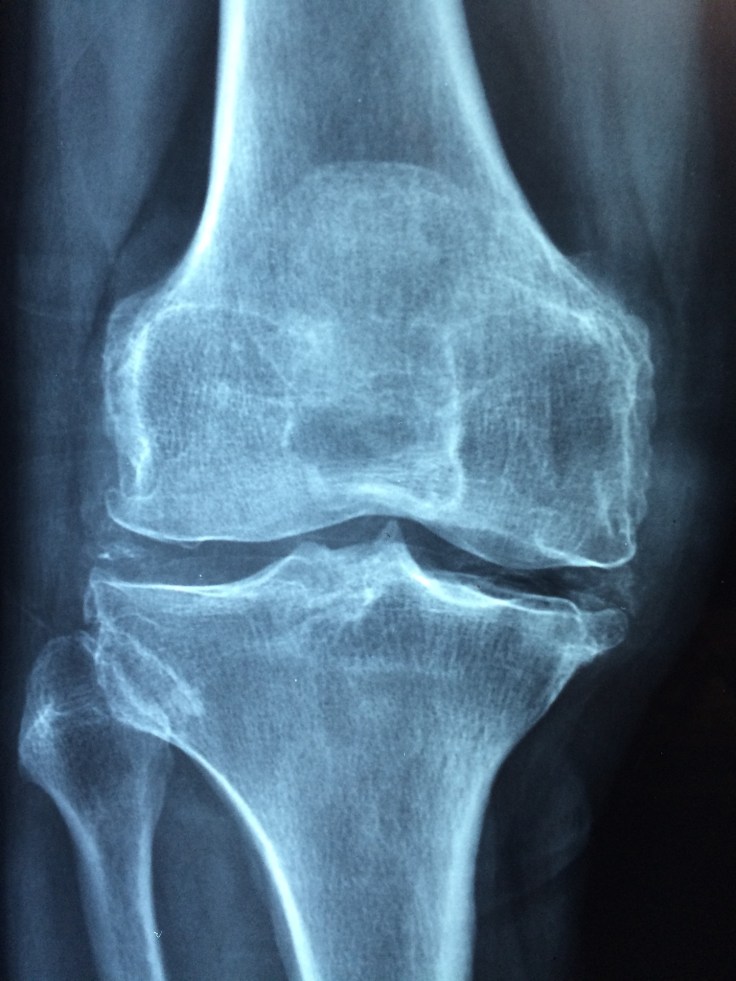

Cauzele sunt multiple. Unele pot fi ereditare, o structură a colagenului, substanța care contribuie la rezistența sistemului osteo-articular, mai aparte, mai puțin rezistent, altele pot fi legate de anomalii structurale pe care organismul le percepe ca fiind străine și le atacă. În unele cazuri poate fi vorba despre agenți infecțioși, bacterii, virusuri, sau poate fi vorba de traumatisme la nivelul articulațiilor respective. Sau despre suprasolicitări într-o articulație. De exemplu oamenii care trăiesc la munte fac mai des gonartroze pentru că trebuie tot timpul să urce sau să coboare în pantă provocând o suprasolicitare la nivelul genunchiului. Excesul de greutate poate fi un factor de risc pentru apariția acestor afecțiuni.

Ce este de făcut ? În primul rând o consultație la reumatologul vostru care vă da o strategie de urmat. Fie că este vorba de medicație, fie că este vorba de alte strategii de lucru, trebuie să vă vedeți des cu el/ea. Pe lângă medicație se pot utiliza mijloacele fizio-terapeutice : băile cu ape sulfuroase, biocurenți, băi galvanice și toate celelalte metode fizioterapice. Apoi dieta trebuie suplimentată cu calciu, vitamină D3, dar și cu mersul la plajă pentru că trebuie să lăsăm soarele să introducă în organismul nostru acel calciu ingerat. Pentru că dacă lipsesc aceste elemente, s-ar putea să le fi luat degeaba doar pe unele din ele. Un alt aspect de luat în considerație este schimbarea stilului de a lucra, merge și a folosi sistemul locomotor. Adică ar trebui să evitați să stați mult în picioare, să mergeți distanțe exagerat de mari pe jos etc.